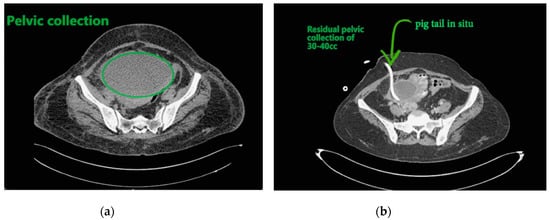

Figure 3. (a) Pelvic collection; (b) showing residual collection in pelvis with drainage catheter in situ.

Contemplating unusual location of air fluid level in an otherwise stable patient, contrast enhanced computed tomography (CECT) of the abdomen and pelvis was done. CECT was suggestive of liver abscess in segment VII, VI which was 300 cc liquified with gas formation within. The abscess had ruptured with collection tracking along the right paracolic gutter till pelvis with 800 cc liquified large collection noted within (Figure 2a and Figure 3a).

The patient underwent ultrasound guided percutaneous abscess drainage and placement of 12-Fr and 14-Fr catheter in liver and pelvic collections respectively. The aspirate was purulent and Klebsiella pneumoniae was detected in cultures. Blood culture was negative even on repeated samples. Gene xpert (CB NAAT) was negative for mycobacterium tuberculosis (MTB). Fluid samples were also negative for malignant cells. She was started on antibiotics Piperacillin and tazobactum combination and monitored for blood glucose levels as a high suspicion of diabetes. Antibiotics was switched to imipenem as per the sensitivity of fluid cultures. She was tested negative for human immunodeficiency virus (HIV). Conservative management was continued as the patient improved with a repeat CECT after 10 days showing complete resolution of liver abscess and 30–40 cc residual collection in pelvis. Her liver enzymes became normal. Drains were removed on day 12 and day 14 from liver and pelvis respectively. She developed an induration of 13 mm when tested for tuberculin skin antigen test at 72 h post inoculation suggesting positive test. Fluid adenosine deaminase (ADA) levels were found to be 250.5 U/L and patient started on category 1 anti-tubercular treatment. Patient was discharged on day 15 without sequelae.